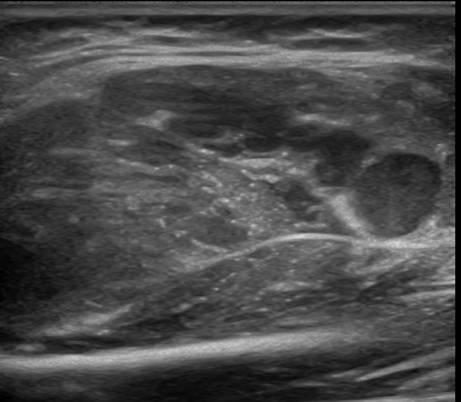

U xơ cơ

» Thông tin: Nữ giới – 3 tháng tuổi.

» Lâm sàng: Sưng vùng đùi.